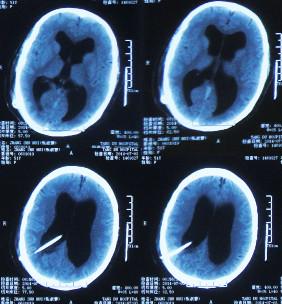

出院后1年零4个月即2015年12月8日(脑室腹腔分流术后1年零5个月),又因“肠梗阻(不全性)”,第2次住入之前手术的医院,当天查腹部CT:仍然有积液(图-6)。给予静脉抗感染、灌肠通便等对症支持,治疗2周后,肠梗阻症状改善后出院。

图-6:2015年12月8日腹部CT

第2次出院后4月余即2016年6月7日,因第3次“发热”就诊当地某医院中医门诊,经中医治疗近两月时间。于2016年6月21日复查头颅CT:幕上脑室仍扩张(图-7)。治疗期间发热曾缓解,但之后发热仍反复。

图-7:2016年6月21日头颅CT

住院次日即2016年8月17日,查腹部CT:仍有腹腔积液(图-8)。

图-8:2016年8月17日腹部CT

住院后3天即2016年8月19日,查头颅CT:幕上脑室扩张(图-9)。

图-9:2016年8月19日头颅CT

第3次出院后21天即2016年9月23日,复查头颅CT:幕上脑室仍扩张(图-10)。

图-10:2016年9月23日头颅CT